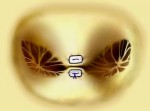

Il diagramma mostra la valutazione della severità dell’insufficienza mitralica usando l’approccio transesofageo con vista asse-lungo. La gravità dell’insufficienza mitralica (1-4+) viene stabilita in base alla lunghezza e alla larghezza del flusso di jet nell’atrio sinistro. LA, atrio sinistro.; RV, ventricolo destro; LV, ventricolo sinistro.

ecocardiografia.jpg

Immagine16.jpg